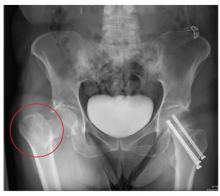

The radiograph demonstrates evidence of contrast material within the bladder. There is evidence of fixation of an old subcapital femoral neck fracture on the left.

There is an acute, mildly displaced right intertrochanteric fracture of the right hip. The orthopedic service was consulted, and plans were established to subsequently fix this fracture surgically.